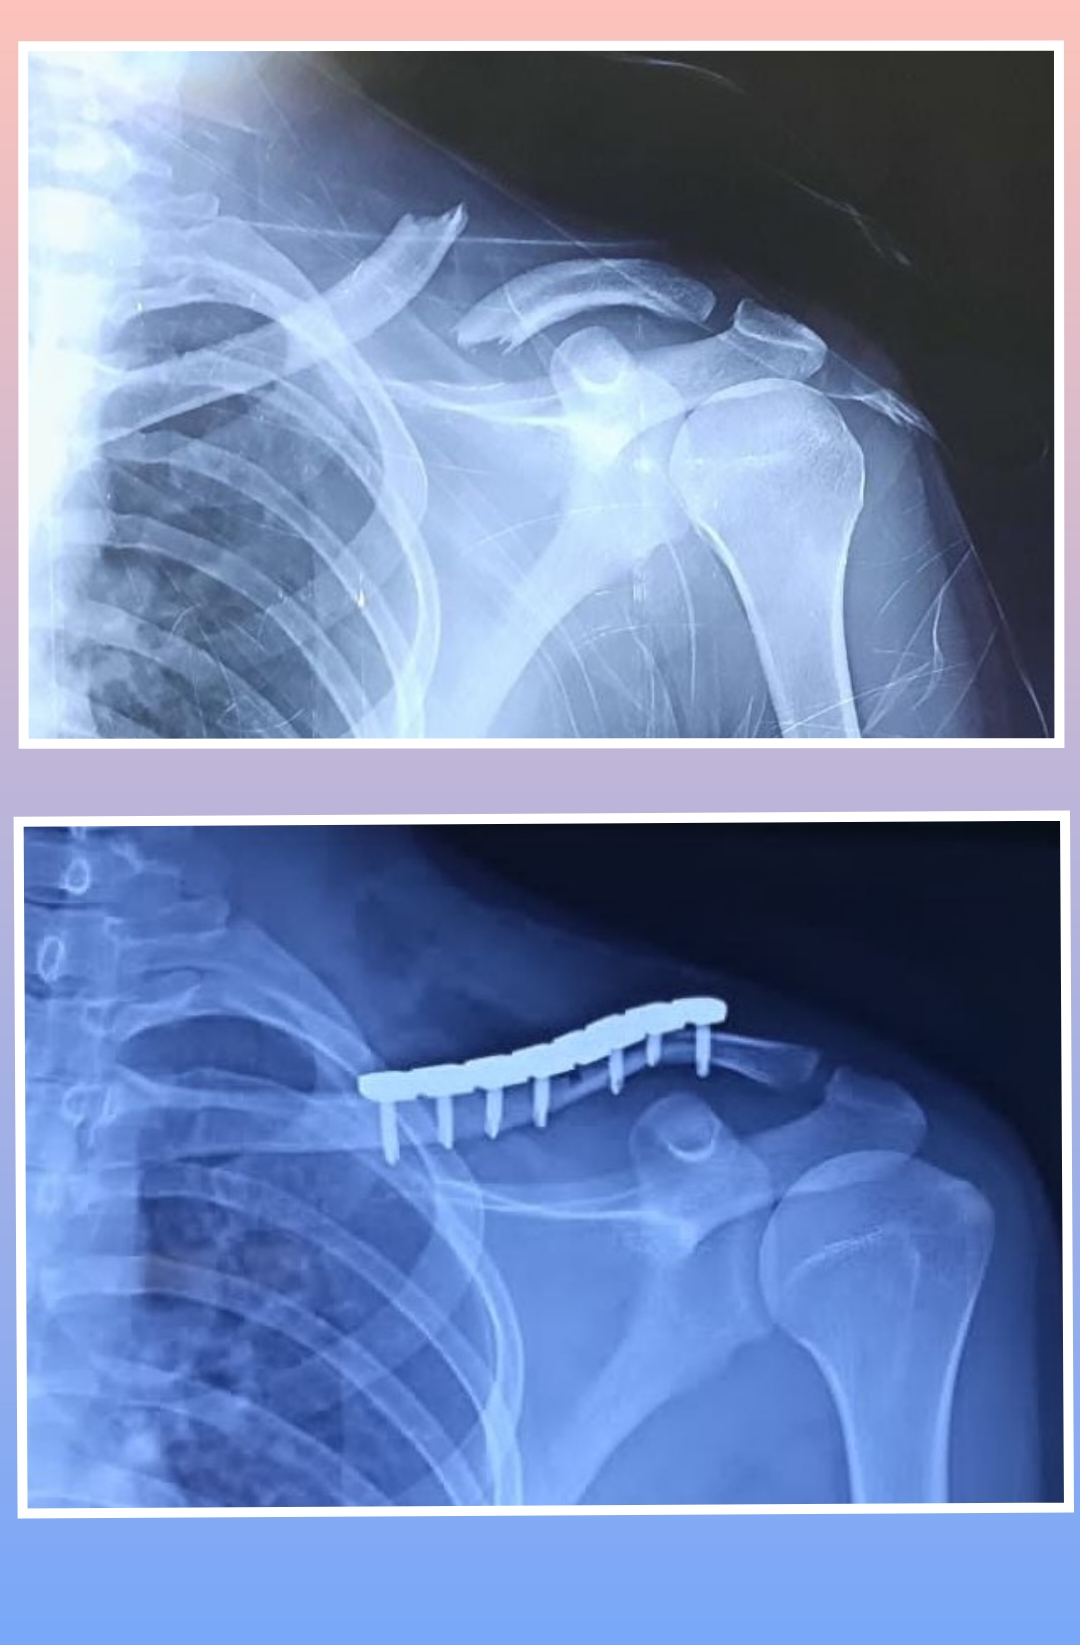

X-ray

Warning: Graphic Content

The following section contains graphic images of surgical procedures. These images are intended for educational purposes and may be disturbing to some viewers. Viewer discretion is advised.

Surgeries